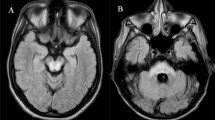

Considering neuroimaging studies, including structural magnetic resonance imaging (MRI), CBS patients typically present an asymmetrical cortical atrophy, involving posterior frontal and parietal lobes, contralateral to the clinically most affected side (MAS) (Constantinides et al. 2019). In addition, CBS showed a more prominent supratentorial pattern of atrophy in comparison with other APs, such as PSP patients, having an infratentorial involvement and symmetric pattern (Whitwell et al. 2014). However, at the early stages of the disease, qualitative evaluation of MRI could not be conclusive for differential diagnosis between PD and CBS. Thus, the use of advanced MRI neuroimaging method with quantitative analysis of cortical structures together with neurophysiological data exploring brainstem excitability could be useful for the differential diagnosis.

MRI data acquisition

Brain MRI was performed according to our routine protocol with a 1.5 T unit (Signa HDxt, GE Medical Systems, Milwaukee, WI, USA). A 3D T1-weighted high-resolution spoiled gradient echo (SPGR) sequence with a 1.2-mm slice thickness and an isotropic in-plane resolution of 0.98 mm was acquired with the following parameters: repetition time 14.8 ms, echo time 6.4 ms, flip angle 25°, 115 slices, matrix size 256 X 256 and a field of view of 24 cm. In addition, all the patients underwent also a T2-weighted and FLAIR images in order to exclude morphological abnormalities, vascular disease or intracranial lesions.

Image analysis

Cortical reconstruction was performed using the FreeSurfer image analysis suite, version 5.3, documented and freely available for download online (http://surfer.nmr.mgh.harvard.edu/). Briefly, this processing includes motion correction and averaging of multiple volumetric T1-weighted images, removal of non-brain tissue using a hybrid watershed/surface deformation procedure, automated Talairach transformation (Fischl et al. 2004), intensity normalization, tessellation of the gray-white matter boundary, automated topology correction and surface deformation following intensity gradients, to optimally place the gray/white and gray/cerebrospinal fluid borders at the location where the greatest shift in intensity defines the transition to the other tissue class (Fischl and Dale 2000). Images are then carefully checked for skull stripping errors. Once the cortical models are complete, a number of deformable procedures can be performed for further data processing and analysis including surface inflation, registration to a spherical atlas which is based on individual cortical folding patterns to match cortical geometry across subjects, parcellation of the cerebral cortex into units with respect to gyral and sulcal structure (Desikan et al. 2006), and creation of a variety of surface-based data including maps of curvature and sulcal depth. This method uses both intensity and continuity information from the entire three-dimensional MR volume in segmentation and deformation procedures to produce representations of cortical thickness, calculated as the closest distance from the gray/white boundary to the gray/CSF boundary at each vertex on the tessellated surface (Fischl and Dale 2000). Individual surface maps are registered to a common average surface and then smoothed using a Gaussian kernel of 10 mm full width half-maximum.

Mean hemisphere cortical thickness volume for each patient was obtained and then attributed to the clinical MAS and LAS. To compute the AI of MRI, we considered global mean cortical thickness of each hemisphere contralateral to the clinical MAS and LAS and applied the following formula: [(Side1 − Side2)⁄(Side1 + Side2)], where the two sides are the mean cortical thickness values for MAS and LAS of each patient.

MRI data

Cortical thickness analysis showed significant differences between groups in total GM volume and in hemisphere volume considering MRI MAS. In addition, AI of MRI was significantly higher in CBS group (Table 2 and Fig. 2B).

AI of MRI cutoff greater than 0.014 (accuracy: AUC = 0.77; p = 0.002), differentiated CBS from drug-naïve PD patients with a sensitivity of 70% (95% CI 34.8–93.3) and a specificity of 85.7% (95% CI 57.2–98.2) (figure S1). Combination of the two AIs showed an AUC of 1.0, with a sensitivity and specificity of 100% in differentiating PD and CBS patients (figure S2).

Considering MRI findings, cortical thickness findings demonstrated that CBS patients had a decrease total and hemisphere GM volume considering MRI MAS and exhibited a higher AI of MRI. Structural MRI studies showed that CBS patients had a typical asymmetrical pattern of cortical atrophy involving fronto-parietal areas (Constantinides et al. 2019) with a prominent supratentorial involvement (Whitwell et al. 2014), and a relatively preserved brainstem anatomy (Kitagaki et al. 2000). In accordance with our findings, Kitagaki et al. (2000) showed that CBS patients had a widespread cortical atrophy involving the whole cortex and a higher hemispheric asymmetric index compared to AD patients (Kitagaki et al. 2000). Again, CBS patients exhibited a decreased cortical thickness compared to healthy controls, an asymmetric pattern of cortical atrophy with a thinner hemisphere contralateral to the MAS, a sparing of subcortical structures (Upadhyay et al. 2016) and a preservation of brainstem structures (Bocchetta et al. 2020). On the other hand, it has been demonstrated that PD patients did not show an asymmetric cortical atrophy despite the presence of an asymmetric clinical presentation (Danti et al. 2015).